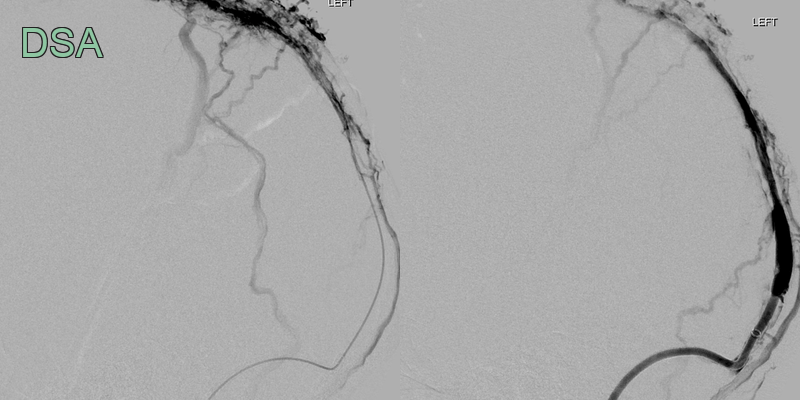

- 50-year-old patient presented with headache and dysphasia.

- CT showed a hyperdense superior sagittal sinus and a lobulated, fractionated, haematoma in the left parietal and occipital lobe.

- Despite a successful venous thrombectomy, thrombus reaccumulated in the superior sagittal sinus and the haematoma enlarged.